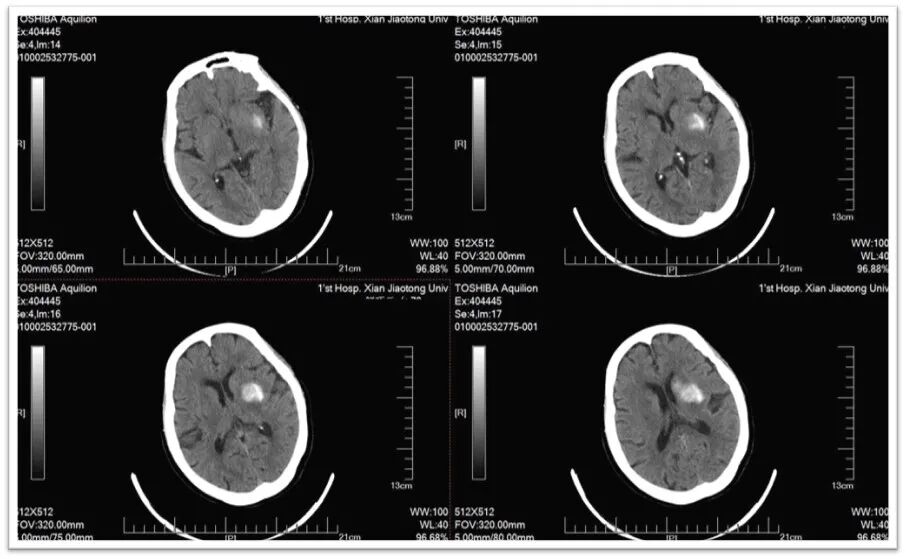

图1:头颅CT提示颅内多发腔隙性脑梗死,脑萎缩;

头颅MRI示:左侧基底节区及侧脑室旁新新鲜梗死灶,左侧颈总动脉闭塞。